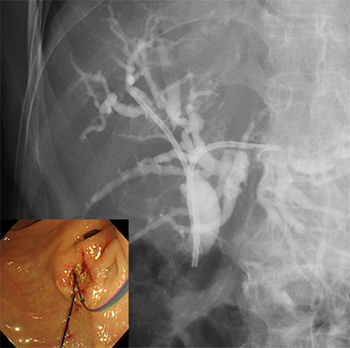

内視鏡的逆行性胆管膵管造影(ERCP)・超音波内視鏡(EUS)による高度な診断治療

胆管炎・胆嚢炎・閉塞性黄疸に対するERCP・EUSによる胆道ドレナージ術・経皮経肝的胆道ドレナージ術(PTBD・PTGBD)

悪性肝門部胆管狭窄に対する

内視鏡的インサイドステント留置術

内視鏡的メタルステント留置術